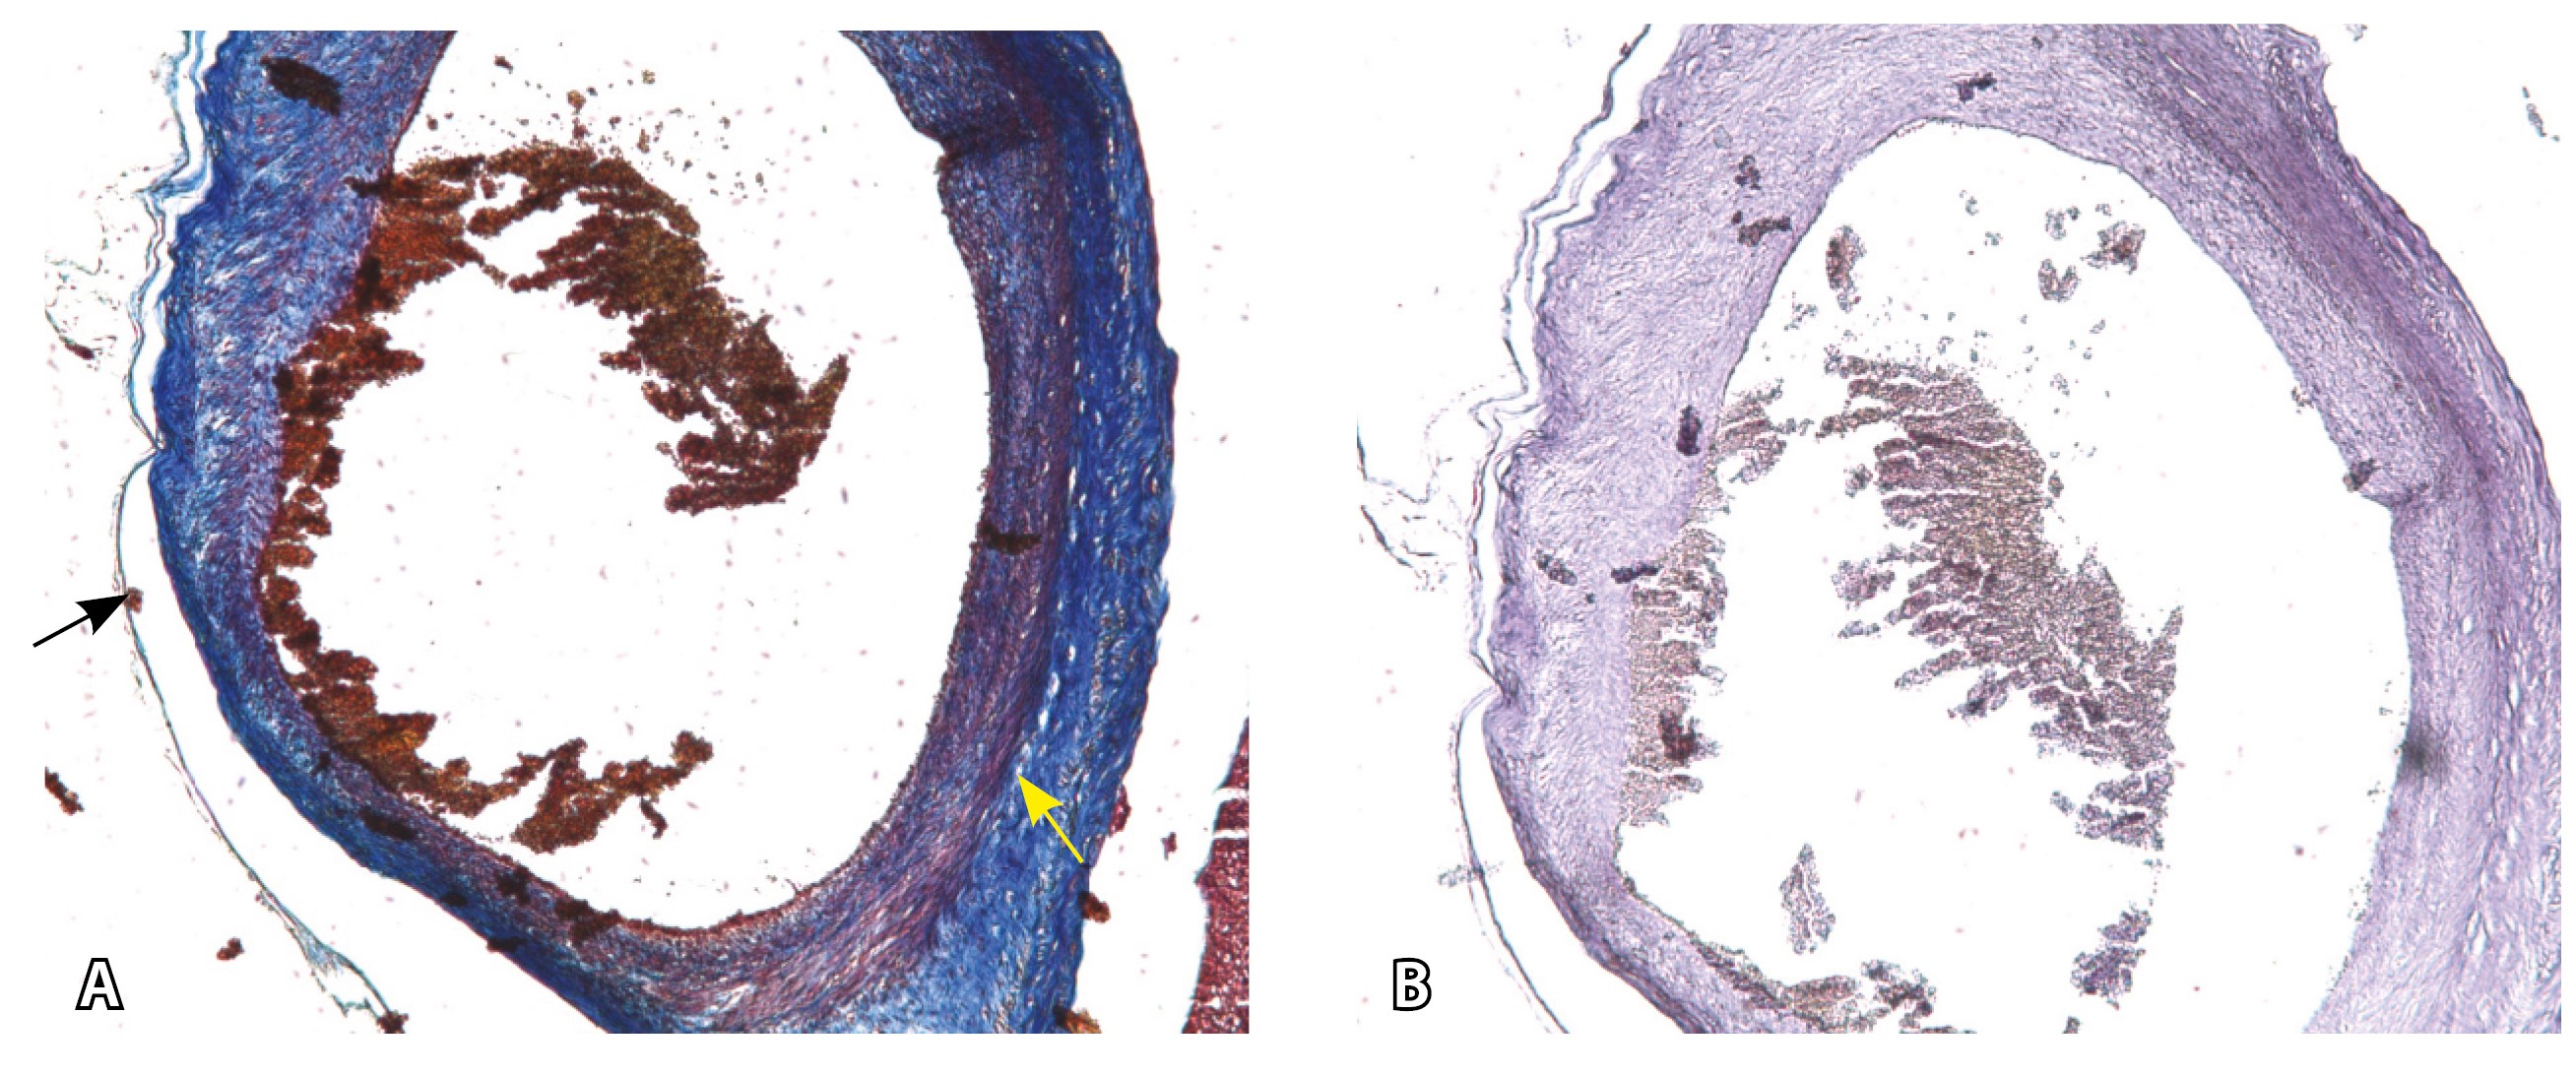

Эластический каркас представлен сетью тонких волокон, без концентрации на внутреннюю и внешнюю мембраны. Однако маркер СD34 констатирует сохранение эндотелия, что свидетельствует о том, что по артериям циркулирует кровь, не сворачиваясь (рис. 13).

Рис. 13. Самые крупные сосуды в пределах серозной оболочки стенки матки: А, Б – серийные срезы артерии; × 50. При окраске по Маллори (А) видна тонкая полоска мезотелия (черная стрелка), слабо дифференцированная мышечная стенка артерии, вокруг нее – плотная коллагеновая оболочка (желтая стрелка), в просвете определяются тромботические массы. При окраске по Вейгерту (Б) наблюдается полная потеря внутренней и внешней эластических мембран